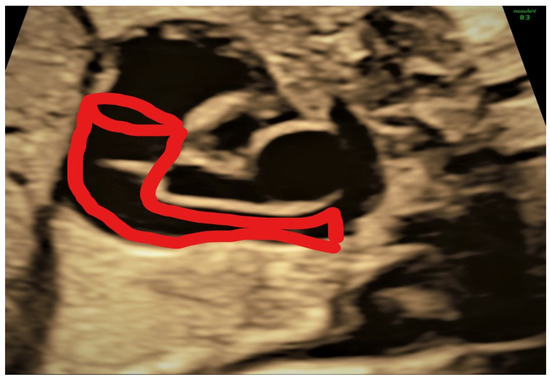

4.1. Case 1